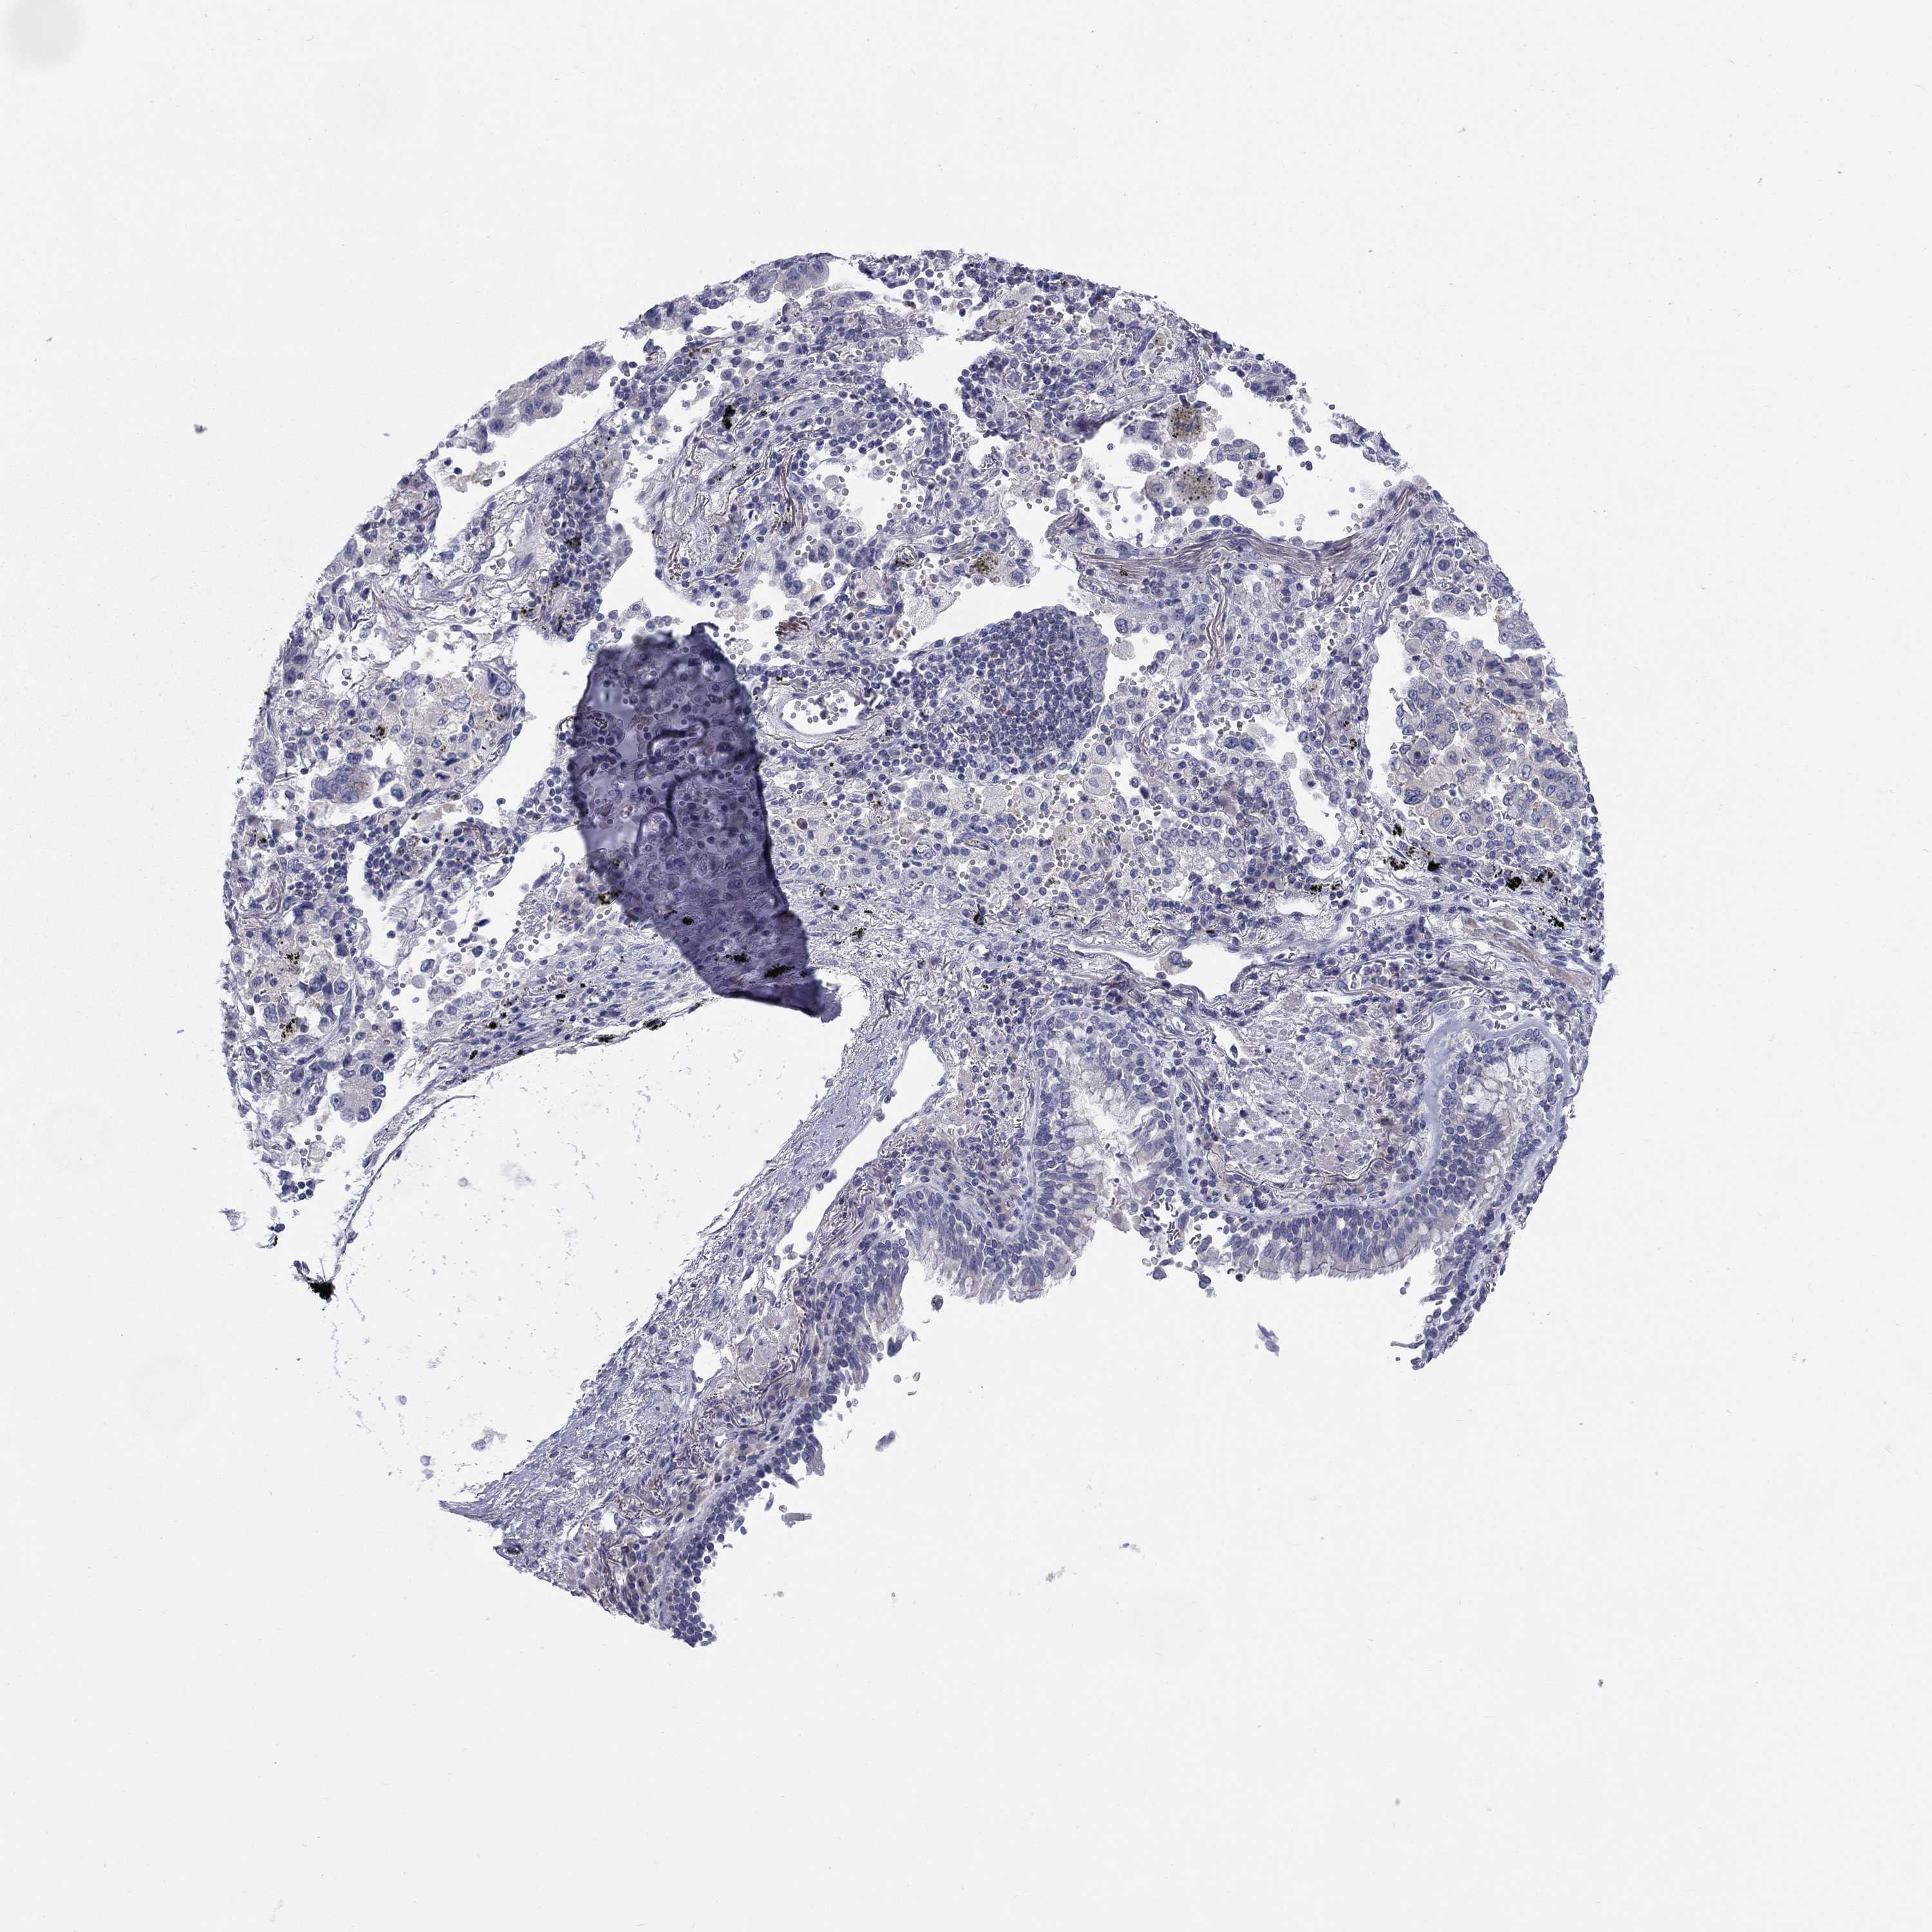

LUNG ADENOCARCINOMA (VALIDATION) - Interactive survival scatter ploti

CACNA1A is not prognostic in Lung Adenocarcinoma (validation)

Average pTPM 0.8

Number of samples 105